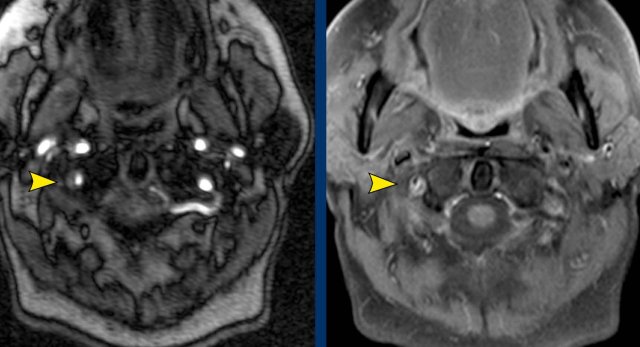

Case

These images are of a patient with a metastatic prostate cancer, who now presents with a paralysis of the hypoglossus on the right and a left-sided Horner.

First look at the images.

Where is the pathology.

Then continue reading.

Images

The left hypoglossus canal is normal.

On the right there is an enhancing mass.

Continue...

The image on the right illustrates the enhancing mass within the hypoglossal canal.

The hypoglossal canal is located between the occipital condyle and jugular tubercle and runs obliquely forwards from posteromedial to anterolateral allowing the hypoglossal nerve to exit the posterior cranial fossa.

In this patient with metastatic prostate cancer we assume that it is a metastasis.

This finding however does not explain the Horner on the left.

Subsequently a CT of the neck and chest was performed, which showed a prevertebral mass at the level of C7-Th1.

This is the exact location of the inferior cervical ganglion.

A mass in this location explains the Horner on the left.